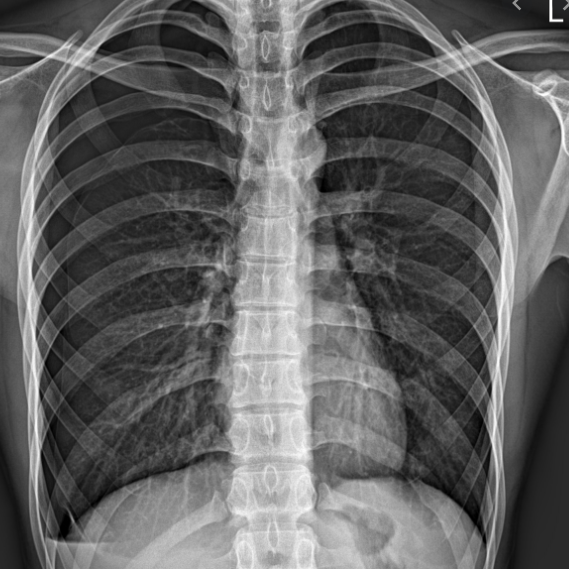

전리방사선 및 비전리방사선의 취급과 방사성동위원소를 이용한 행의학검사와 초음파검사 등 관리 및 취급 업무를 하는 사람을 말합니다. 보통 병원에 가서 엑스레이 검사를 하거나, CT, MRI 검사를 하는 사람들이 방사선사이고, 핵의학과, 방사선종양학과에서 일하는 사람도 방사선사입니다.